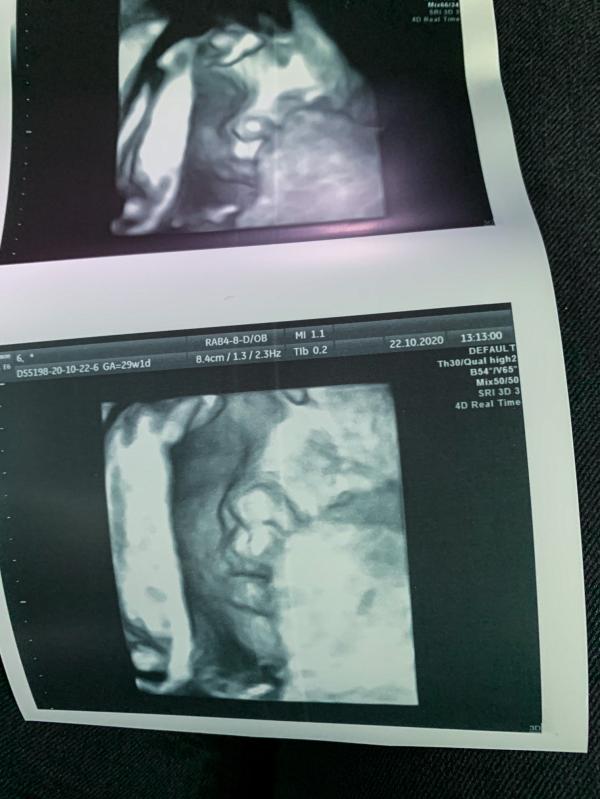

Мы уже совсем скоро родимся

МесЯцев 6 у нас проблема с выбором имени

Как же приятно выходить после УЗИ счастливой с улыбкой до ушей, как вспомню свой второй скрининг вообще ужас( хотя не менее лучший врач был), вышла будто ведро помоев вывалили на тебя.. и ты ещё за это заплатил🙄.

По этому, если идти, то только туда, где ты уже был и знаешь, как все будет проходить.

Все прошло, как и в первую беременность прекрасно, хоть и доча уже закрылась , все равно нам показали ее и сделали хорошие снимки... 😊

Мы как увидели с мужем на экране дочку, сразу сказали друг д...